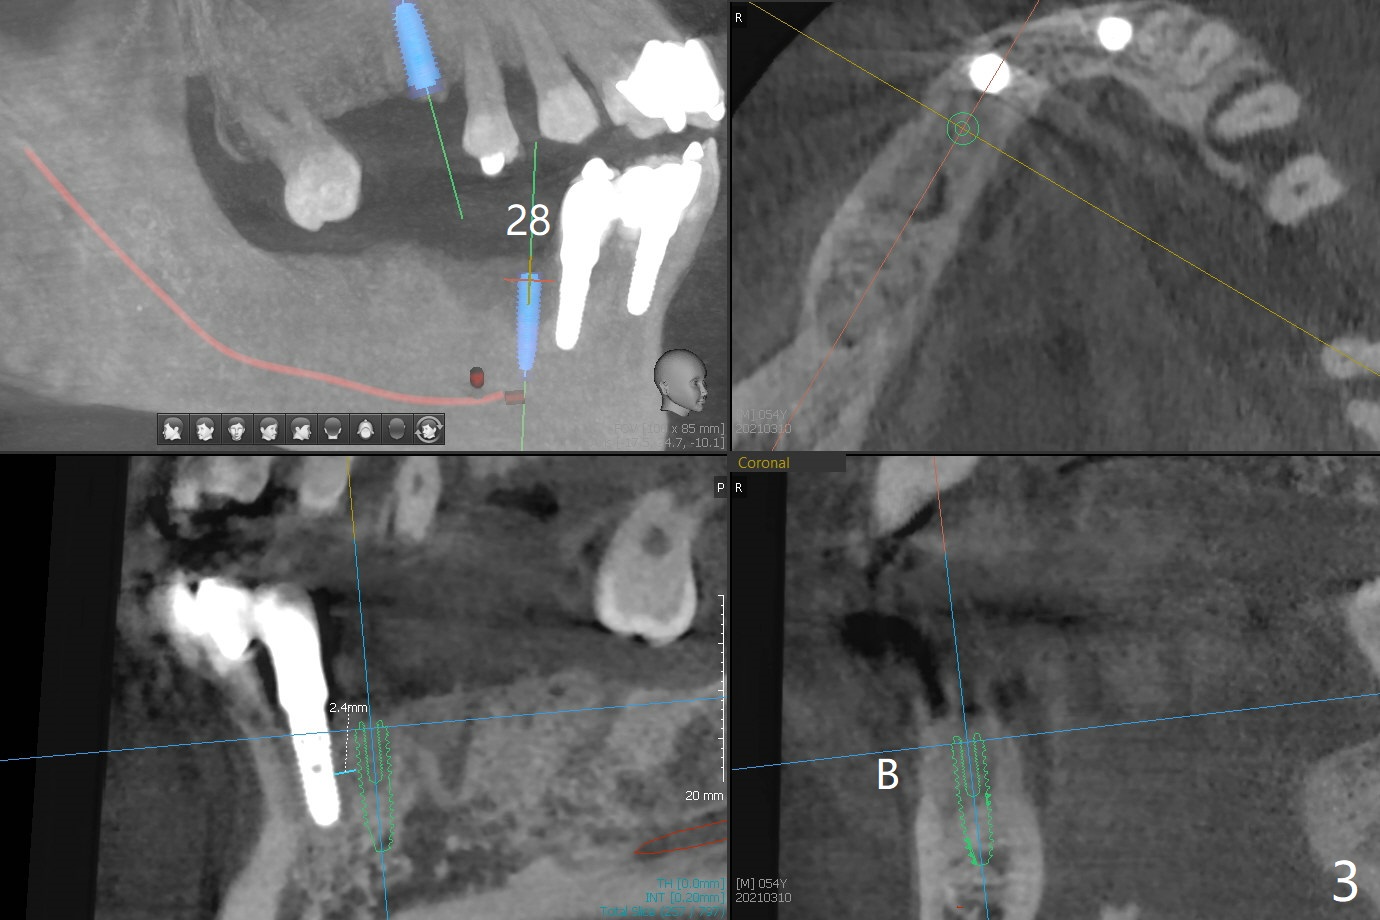

54岁男,28,29植骨后5个月,回来要求3,13,28,29种植(图一)。3号牙需要切开除去残根(图二:*),然后导板种植,准备两个PRF膜。为了保证植牙间距离,尝试在28,29处植入3.5x13毫米植体(图三,四)。在13号牙种植时(图五),考虑12号牙腭侧植骨(图六)。为了减少对12号牙咬合创伤,考虑4个植牙即刻修复。